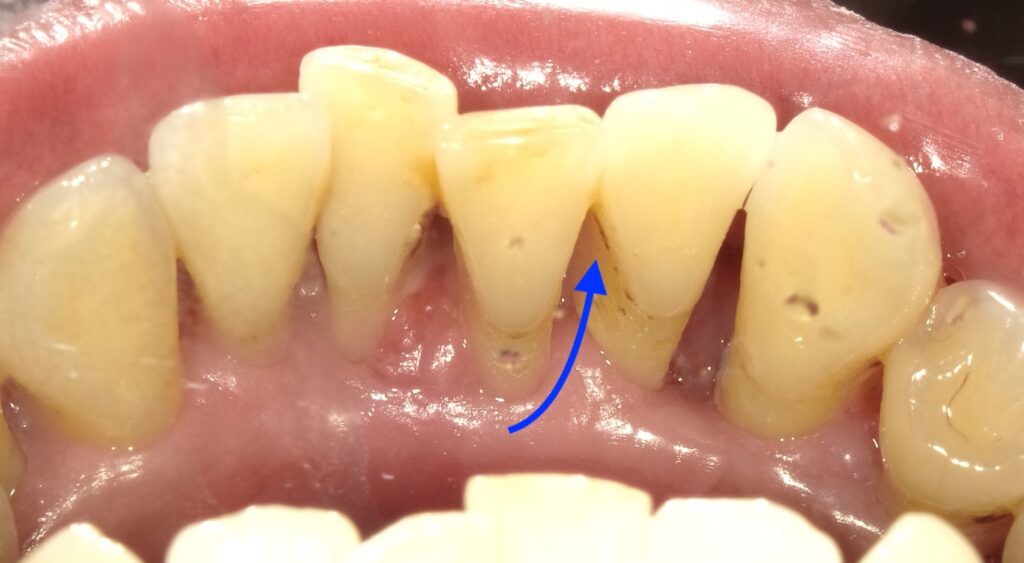

歯肉縁上歯石を取った後の矢印の黒い部分が歯肉縁下歯石になります。

歯周ポケット内の滲出液のカルシウムやリンが歯垢と結合し

できます。これも機械でないと除去できません。また歯石には歯周病菌が

付着するため、炎症反応により歯槽骨という歯を支える骨を溶かして

いきます。